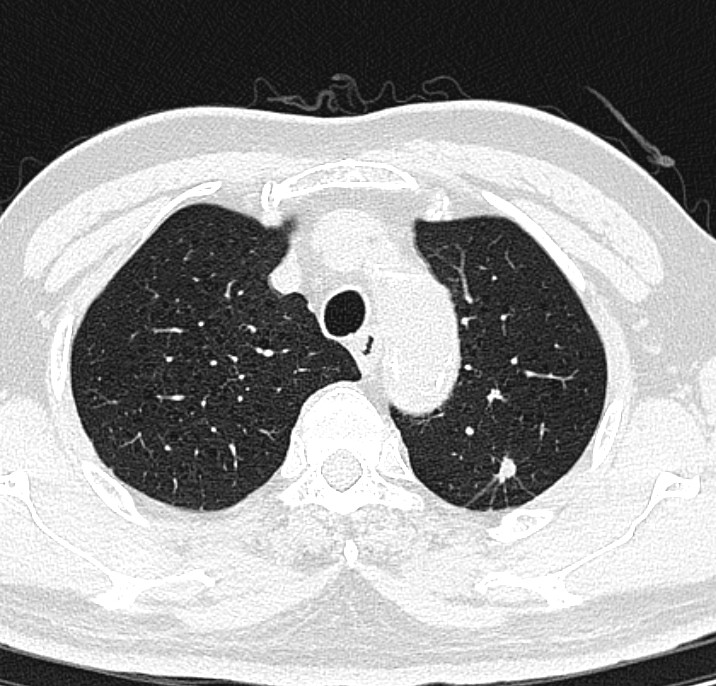

2. CT检查:CT检查具有更高的密度分辨率和空间分辨率,能够发现更细微的病变。在肺部疾病的诊断中,CT尤其是高分辨率CT(HRCT),可以清晰地显示肺部的微小病灶,对于早期肺癌的筛查具有重要意义。通过CT检查,医生能够观察到肺部小结节的大小、形态、边缘、内部结构等特征,从而判断其良恶性。在神经系统疾病方面,CT可用于检查脑出血、脑梗死、脑肿瘤等。在腹部疾病诊断中,CT对肝脏、胆囊、胰腺、脾脏等器官的病变也有很好的显示效果,如肝囊肿、肝癌、胆结石、胰腺炎等。

左肺上叶肺结节和右侧基底节脑出血